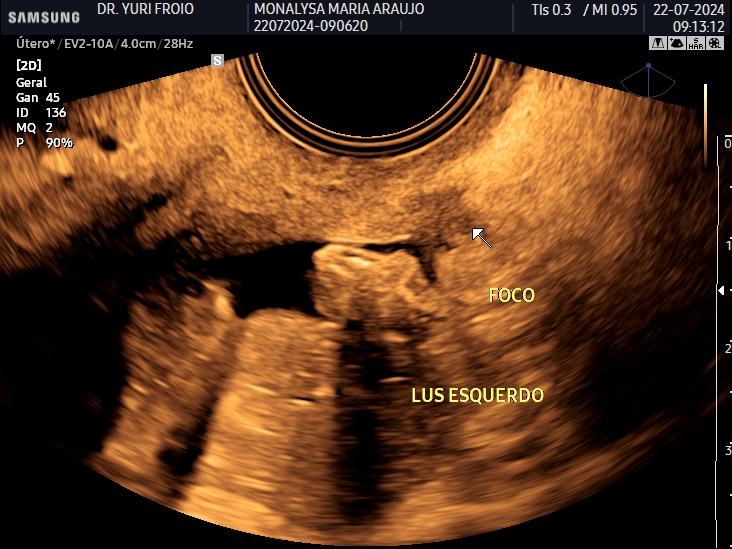

Ecografia Vascular com Doppler

A ecografia vascular com Doppler avalia o fluxo sanguíneo em artérias e veias identificando obstruções, varizes e tromboses. É um exame não invasivo, essencial para diagnóstico e acompanhamento de doenças vasculares. Proporciona informações detalhadas para uma abordagem clínica precisa.